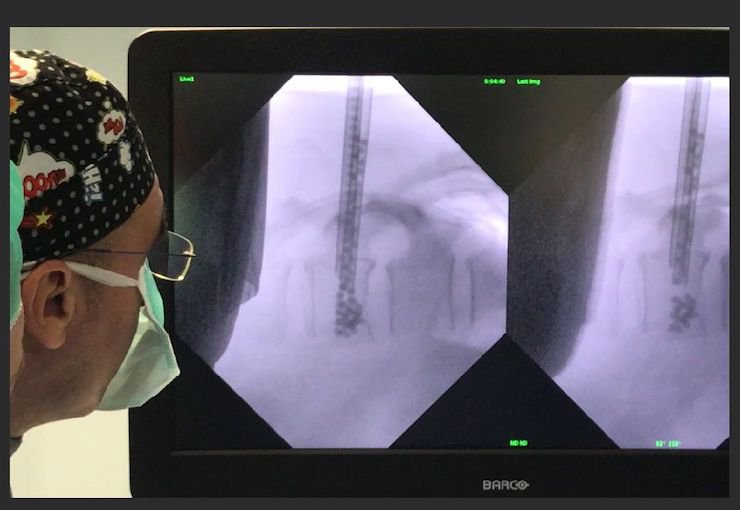

A close collaboration between surgeon and MT Ortho engineers sees a CT scan of the specific anatomical characteristics of the patient carried out, a conference call held to identify access routes and then the characteristics of the fixing systems be determined with consideration given to the resistance of the material being used. The prosthesis is designed and reviewed by the surgeon, before being printed, along with a backup part, and post-processes with washing and final sterilisation.

Using this process, MT Ortho has developed a new line of customised cranioplasty prostheses which are now in use throughout Europe and also created solutions for orthopaedic surgery, Oncological orthopaedics, neurosurgery and maxillofacial surgery. In bone cancer treatment, the design freedom enabled by additive manufacturing allows for the development of customised prostheses that consider deformation and the need to adequately distribute loads, while also perfectly reconstructing bone anatomy after demolition surgery is carried out to remove tumours based on the CT imagery.